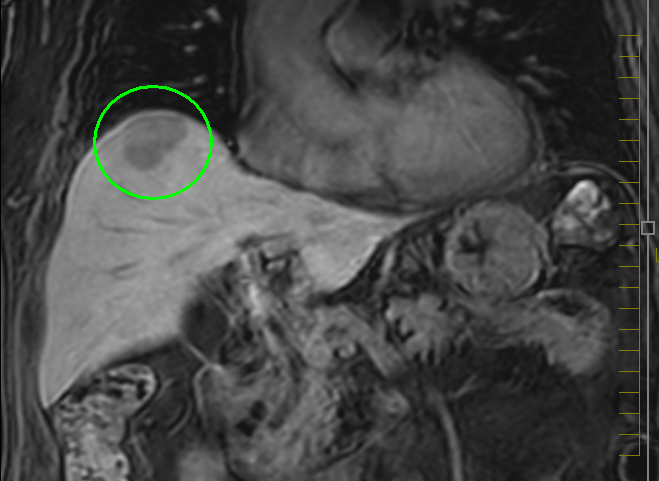

肝臓がんの検査としては、まず血液検査(肝機能検査、腫瘍マーカー検査)と超音波(エコー)検査を行います。必要により、CT検査もしくはMRI検査による画像検査も組み合わせて実施します。画像検査で良性/悪性の鑑別が難しい場合は、直接腫瘍組織を採取して調べる検査(針生検)を追加する場合もあります。

MRI画像